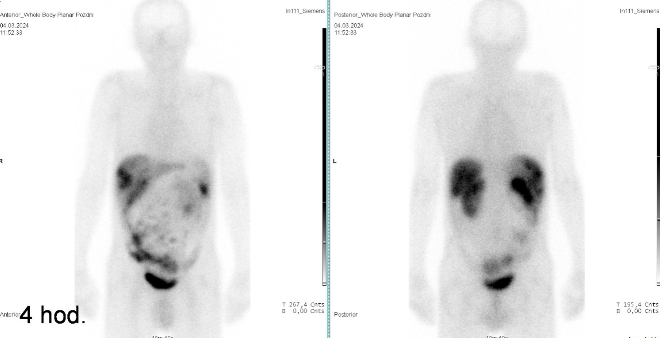

I. v. jsme aplikovali 190 MBq analogu somatostatinu značeného 111In

(přípravek OctreoScan firmy Curium Netherlands B. V.) a provedli pomocí hybridní tomografické scintilační kamery Symbia Pro.specta X7 firmy Siemens opatřené kolimátory pro střední energie planární celotělovou scintigrafii a cílenou tomografickou scintigrafii (SPECT) břicha a pánve s ldCT za 4 a 24 hod.

/ Obr. č. 1: Celotělová scintigrafie 4 hod. po aplikaci OctreoScanu.

/